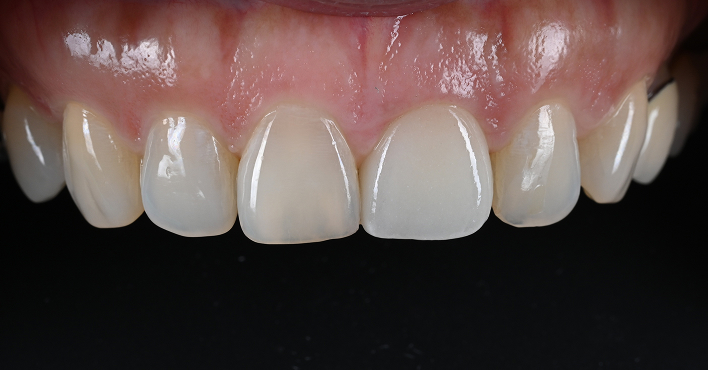

당일 완성된 구강 내 모습

리봄치과의 임상증례 공개는 자신감입니다.

BEFORE & AFTER

01임플란트2023.06.02 - 2025.03.26

BeforeAfter